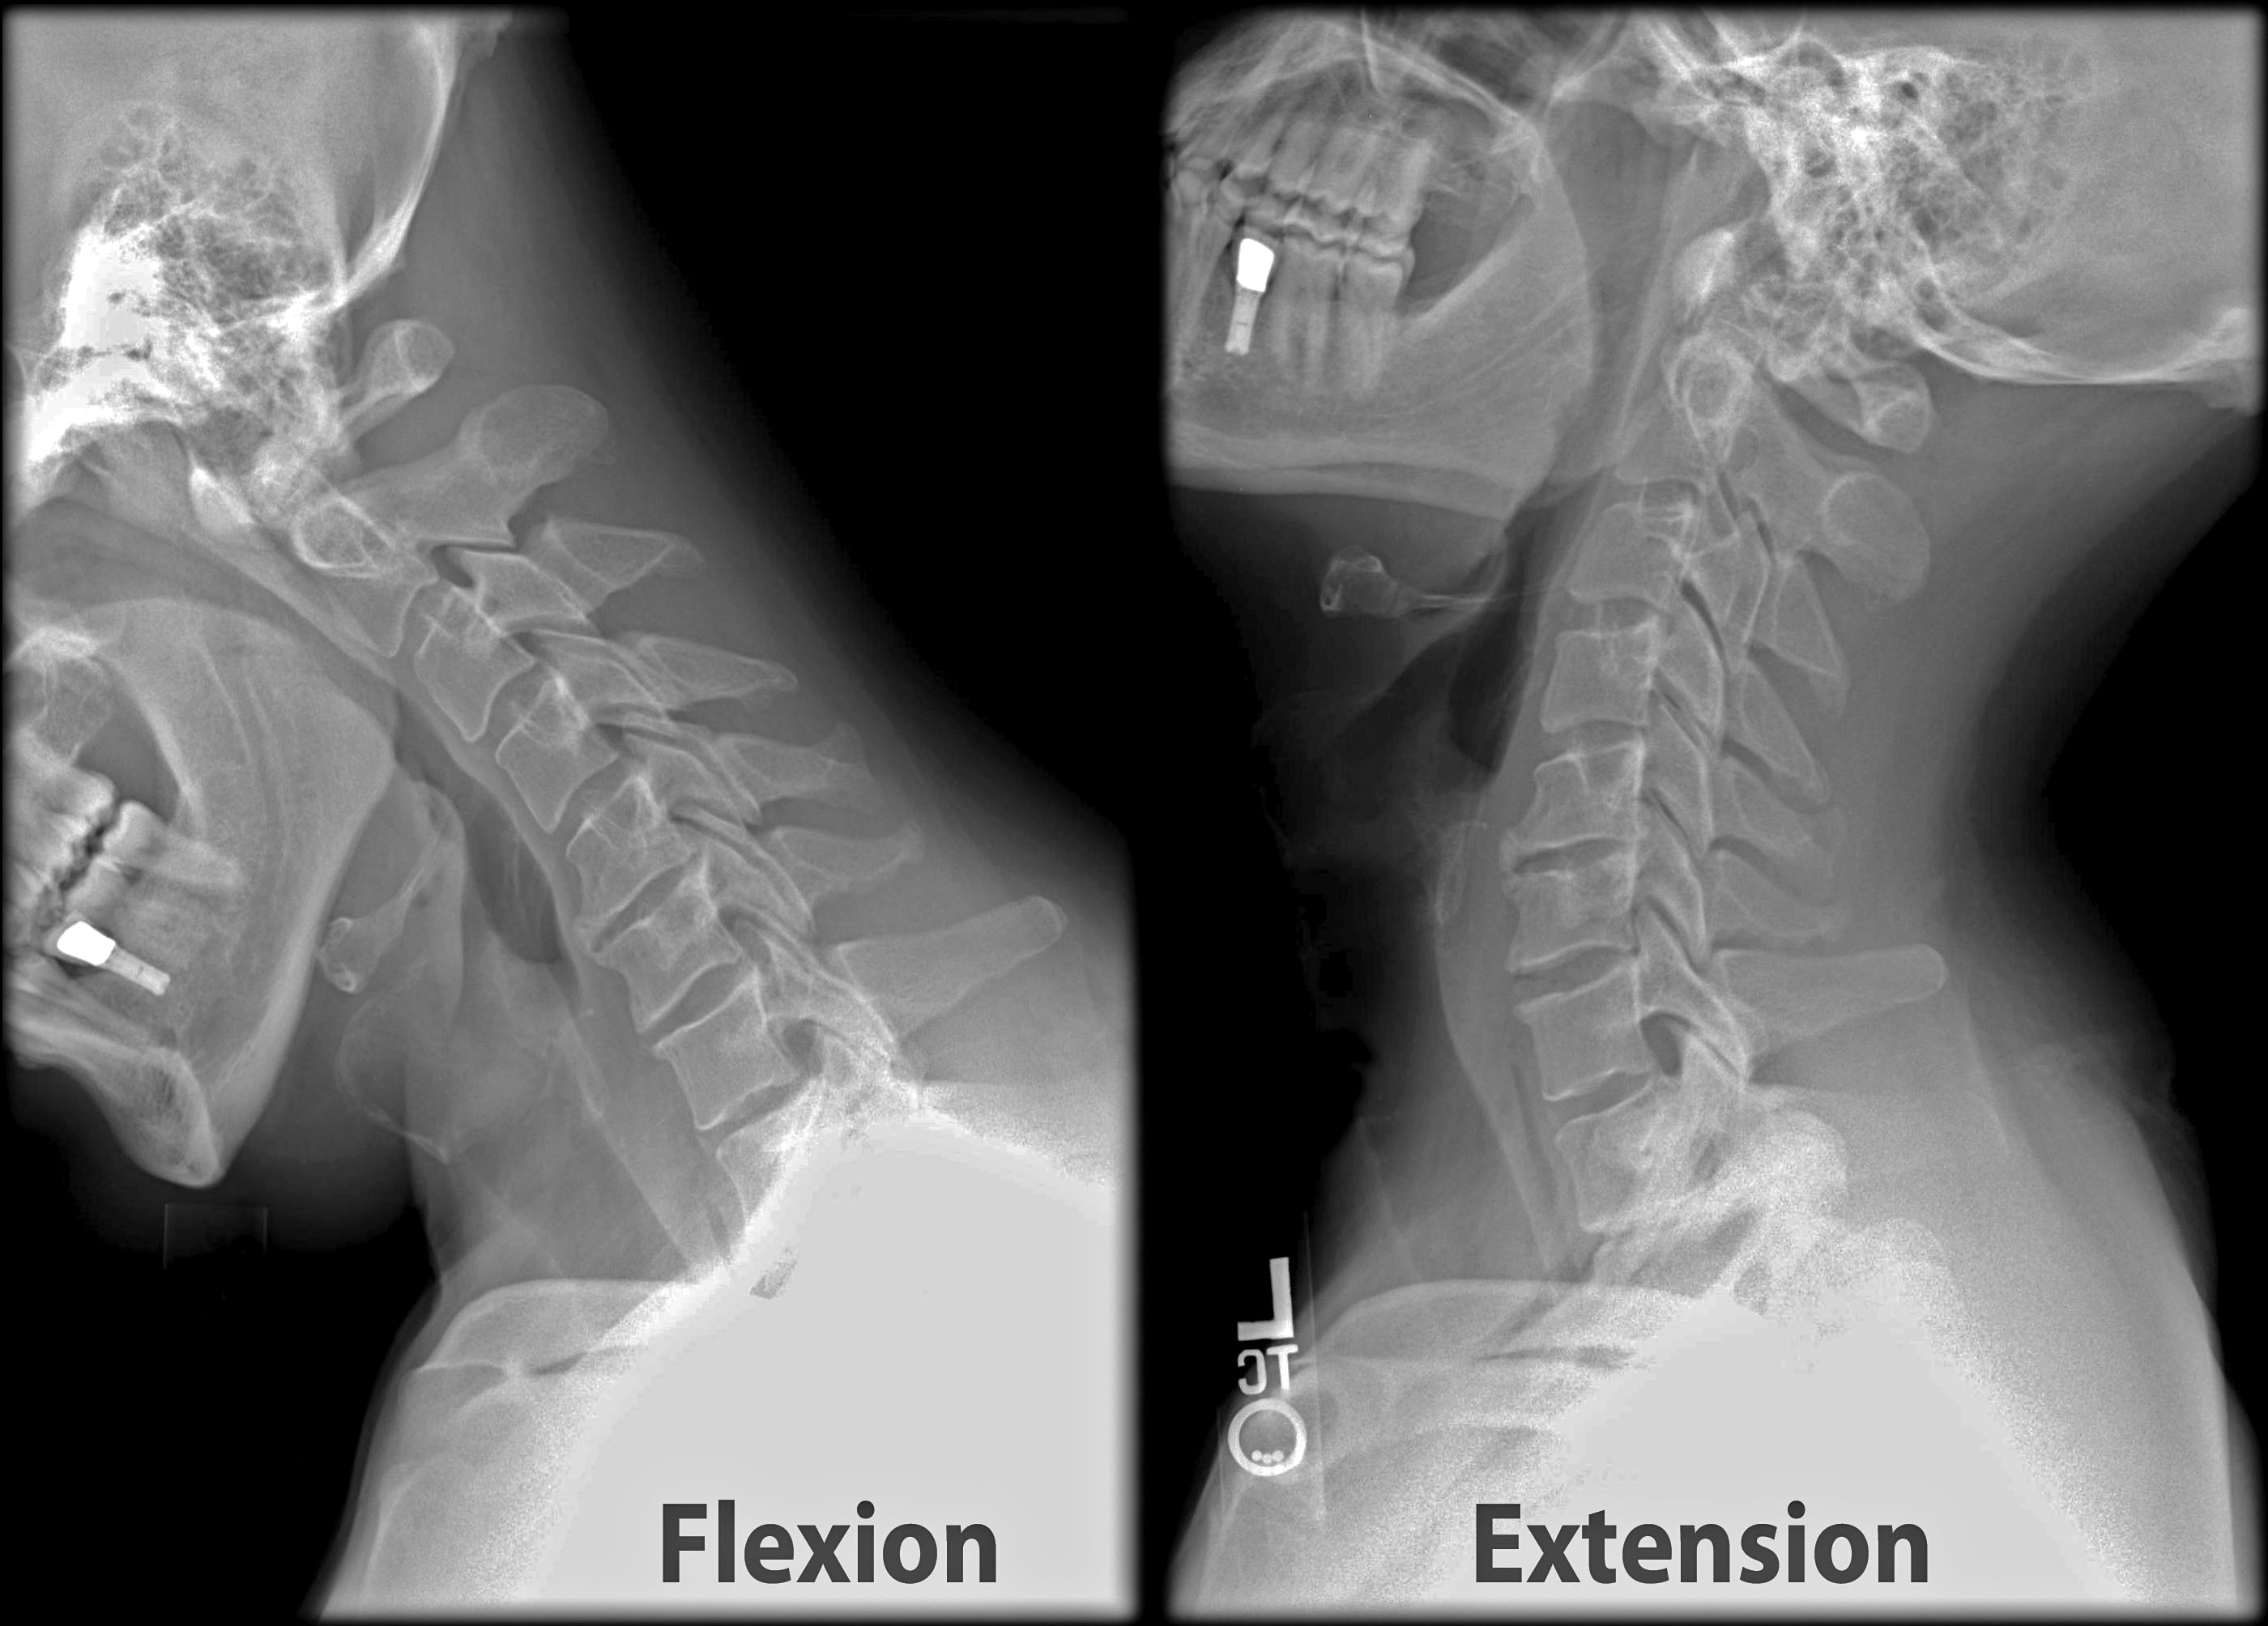

Your doctor might additionally recommend a series of imaging procedures to identify the root cause of your neck and back pain. These imaging procedures can include x-rays, bone scans, and also CT scans. These imaging treatments can be handy, however they aren't necessarily necessary for many instances of neck and back pain. If you have serious back pain, your physician may suggest a shot. These injections can assist to ease discomfort and also reduce inflammation.

A physical therapist can help you find out to reinforce your core muscles, so you are much less most likely to suffer an additional back injury. They can also teach you how to do exercises in your home. You may be advised to do flexion as well as extension workouts to reinforce the muscular tissues that support the spine. You may likewise be instructed to do stretching exercises to unwind your muscular tissues.

Your doctor might additionally advise a physical therapist. A physiotherapist can deal with you to help you establish a personalized exercise program. They will certainly likewise have the ability to assist you enhance your core muscles and other sustaining muscle mass. You might likewise be advised to do flexion as well as extension exercises, and also you may be given a home exercise program.